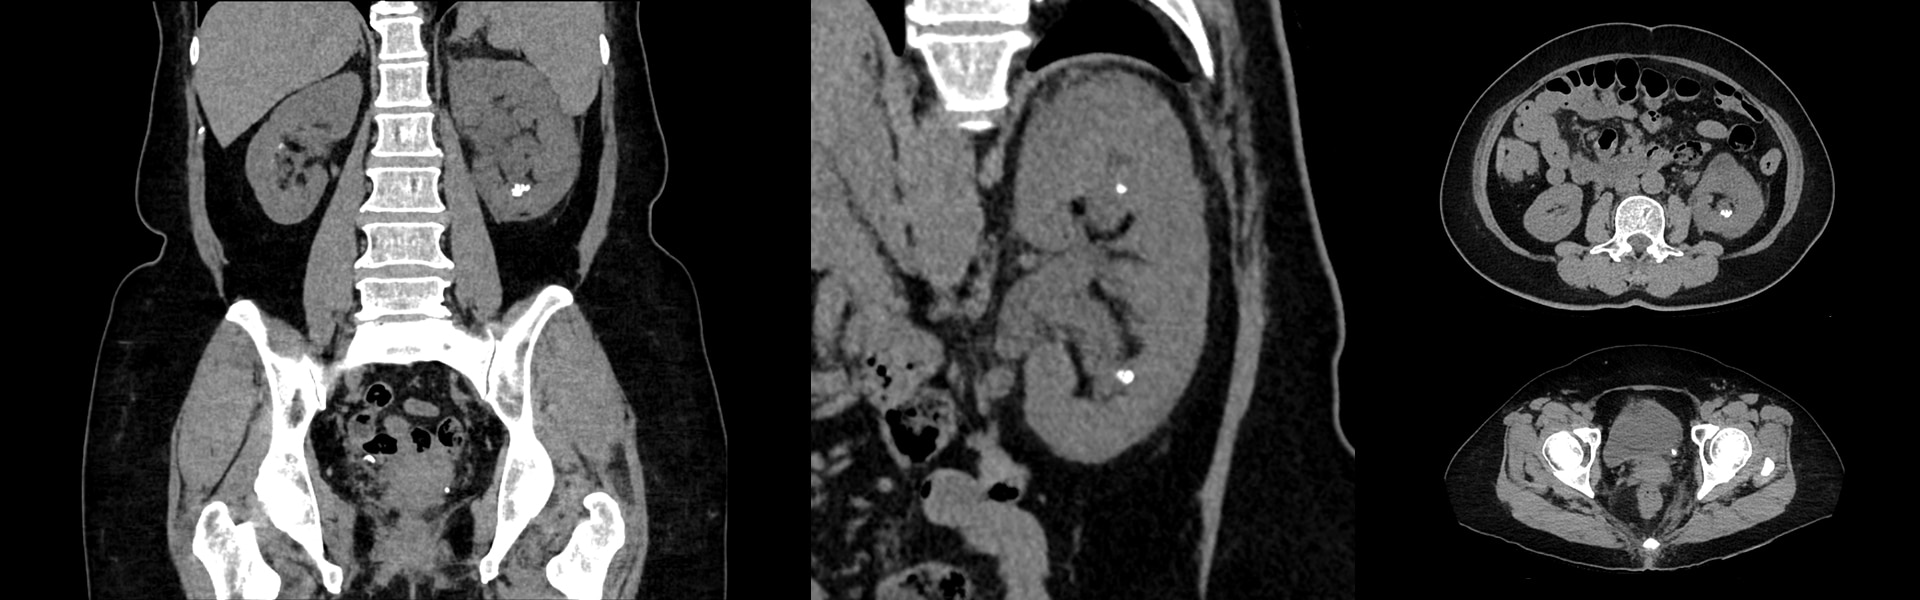

Digital algılamada yeni dönem

Discovery MI Gen 2, çözüm sunmak üzere tasarlanmıştır

- Ölçeklendirilebilir görüntüleme alanı

- NECR'de yüzde 50'lık artış

- cm başına sıra dışı hassasiyet (cps/kBq/cm)

- Tarama süresinde yüzde 33 azalma

- Verilen dozda yüzde 33 azalma